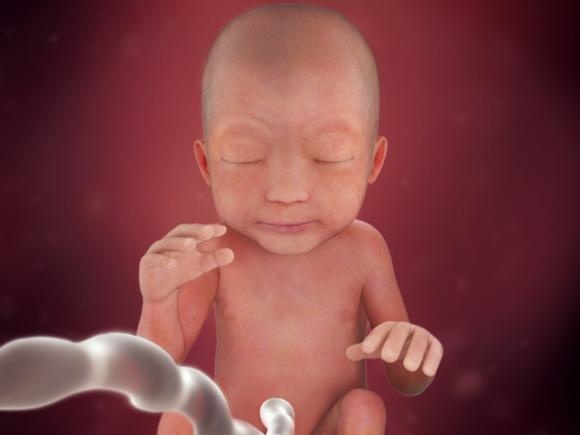

Vaše miminko od minulého týdne přibralo zhruba 100 gramů, už tedy váží přes půl kila a měří téměř 30cm. Takže jako dlouhé pravítko, které si určitě pamatujete ze školních lavic. Jeho tělíčko je stále hubené ale už se pomalu začíná vyplňovat tukem, proto se již brzy bude pěkně kulatit. Již se mu začínají aktivovat chuťové pohárky a v plicích se tvoří plicní sklípky.